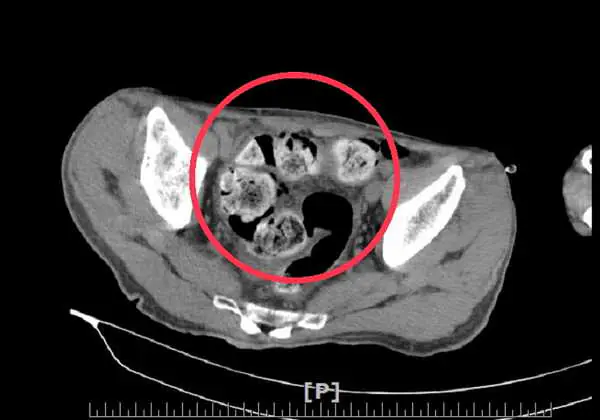

廖師賢主任表示這位病人長期有慢性便秘的問題,也曾因為腸阻塞而住院治療過,這次因為下腹疼痛難受而就醫,透過電腦斷層檢查診斷為糞性結腸炎合併結腸穿孔。經緊急安排手術介入,將破裂的腸道切除、清理腹腔、裝置腸造口並取出許多硬如石頭的糞便,病人住院期間接受專業的醫療處置及照護,恢復良好,已康復出院。

圖文:長期便秘別輕忽 男三週沒拉屎竟把腸子撐破。

長期便秘別輕忽 男三週沒拉屎竟把腸子撐破